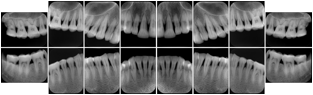

- OO-1. Intra-oral Full Mouth Series Structured Display